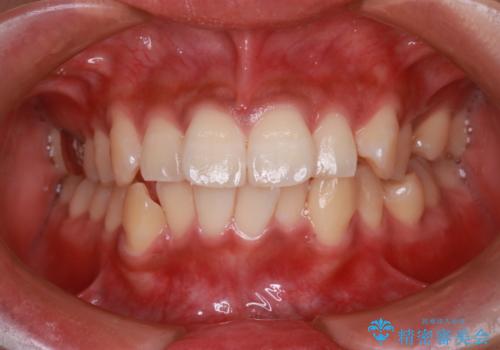

前歯が前に出ているため口元が突出し、唇が閉じにくいなどの悩みを抱えておられました。治療にあたり上下左右の第一小臼歯を抜歯し、十分なスペースを作ることで前歯を効果的に後方へ移動させました。装置には透明で目立ちにくい審美ブラケットを採用し、治療中の審美的ストレスを軽減しました。定期的な調整を通じて無理なく確実に歯列を整え、前歯の突出感を解消。治療後は口元の印象が自然で美しく改善され、患者様には非常にご満足いただけました。